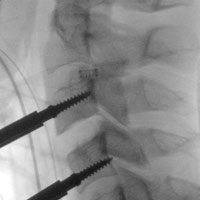

Few complications have been reported to date in the literature for cervical arthroplasty as is shown being performed in this case to implant the Prodisc-C prosthesis [Synthes].

Studies have shown cervical disc arthroplasty procedures like this to be as safe and effective as anterior cervical disc fusion or ACDF. Images: Janssen ME